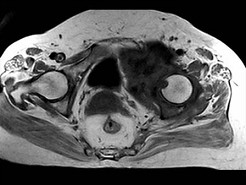

[单选题]患者,男,38岁,左髋部疼痛,并逐渐加重,体检:左髋部明显肿胀压痛,无明显发热,结合所提供的图片,最可能的诊断是()A .骨巨细胞瘤B .纤维肉瘤C .骨肉瘤D .软骨肉瘤E .软骨黏液纤维瘤

[单选题]患者,男,38岁,左髋部疼痛,并逐渐加重,体检:左髋部明显肿胀压痛,无明显发热,结合所提供的图片,最可能的诊断是()A . 骨巨细胞瘤B . 纤维肉瘤C . 骨肉瘤D . 软骨肉瘤E . 软骨黏液纤维瘤